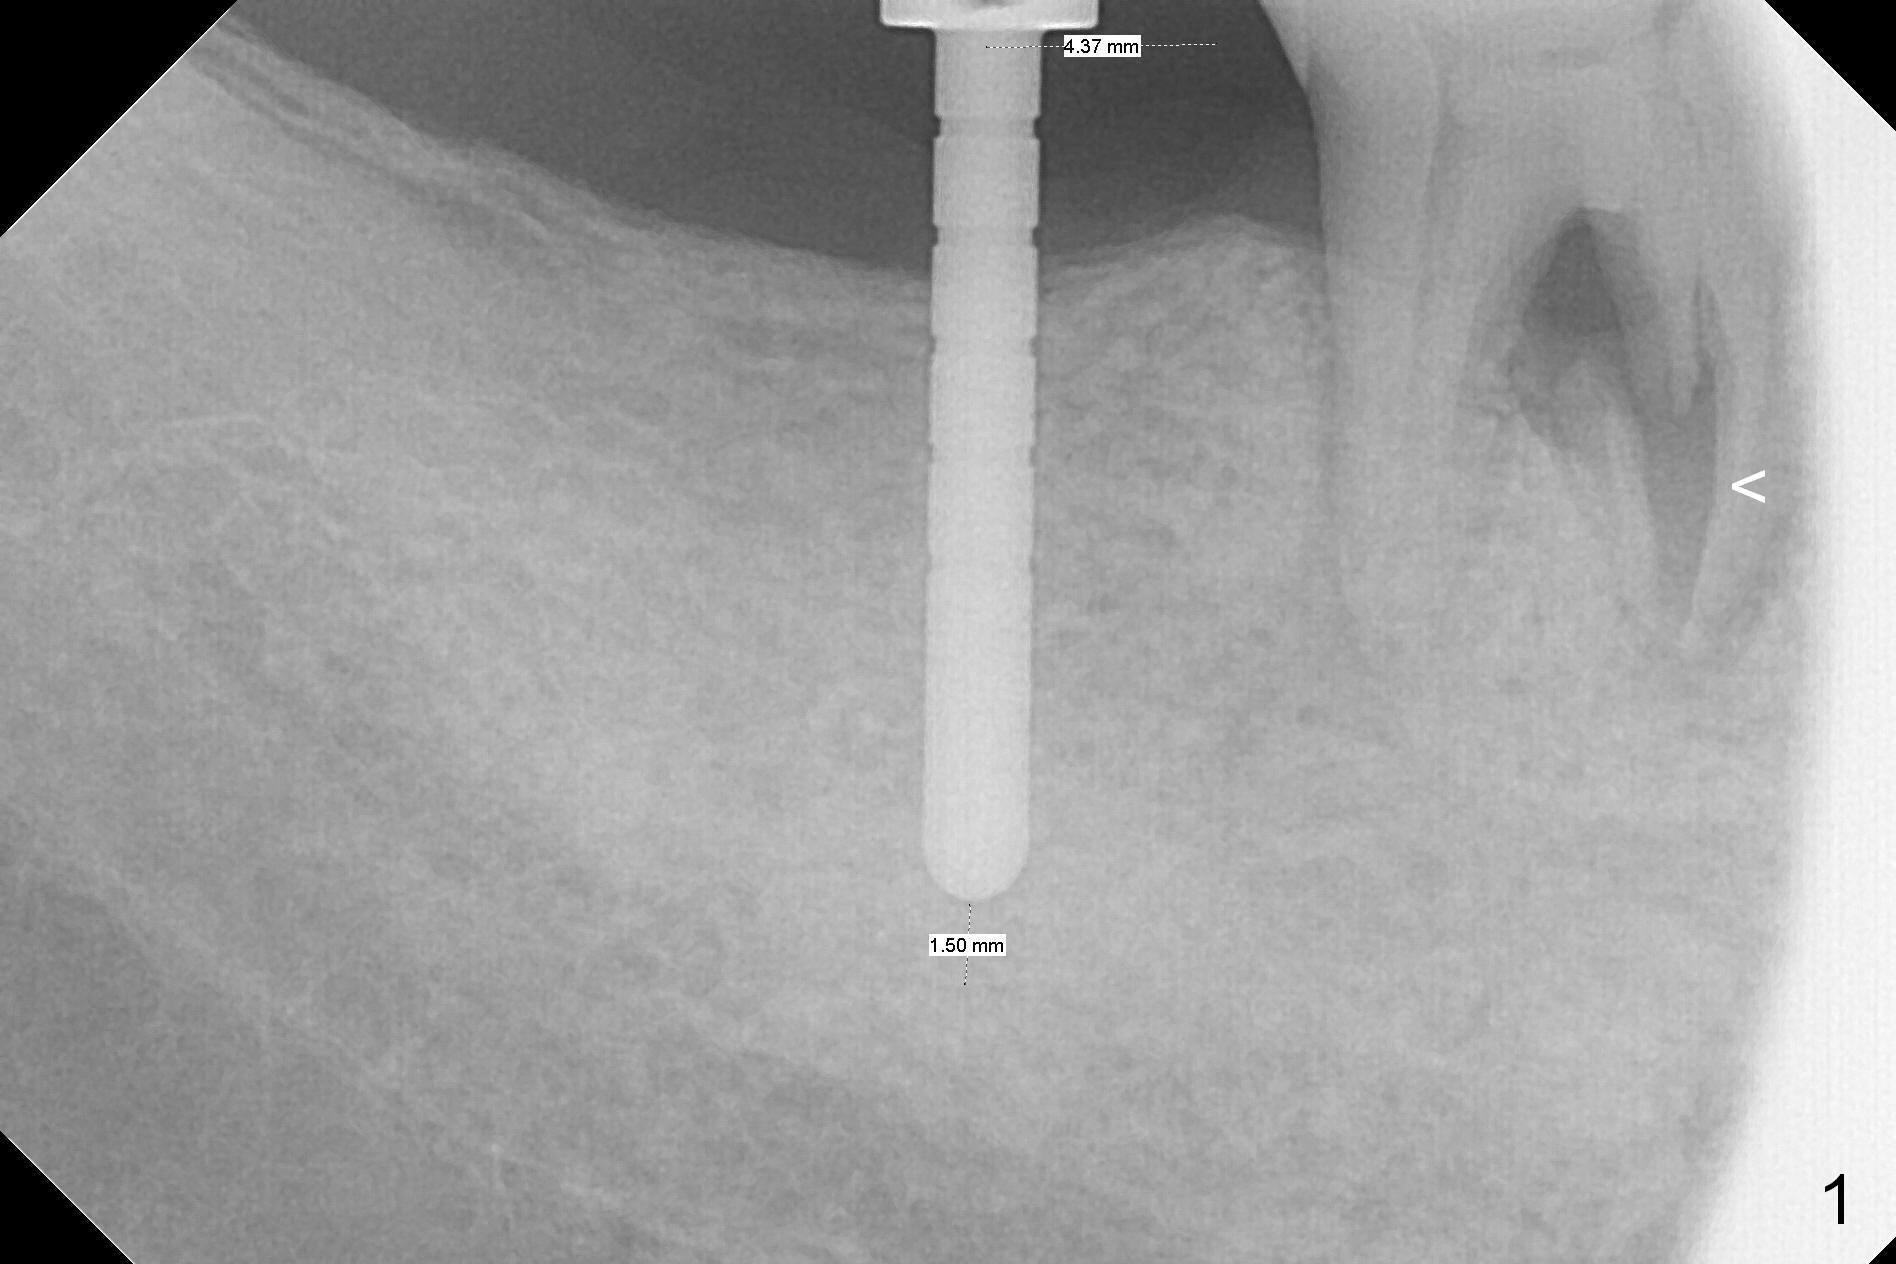

The leukoplakia at the sites of #31 and 32 is most likely related to smoking and the supraerupted teeth #1 and 2 (Fig.0 ^).  After osteotomy for 11.5 mm at #31 (Fig.1), it appears that the bone height is not as much as expected.  The last two drills for sequential osteotomy are 4.3x13 and 4.8x11.5 mm.  A 5x11.5 mm UF implant is placed slightly subcrestal with insertion torque > 50 Ncm (Fig.2).  Following placement of 6.5x2 mm healing abutment, the opposing tooth needs adjustment for height.  Orthodontic intrusion of the opposing tooth is scheduled 2 days later.  It is accidental to find root fracture of the mesial root of the tooth #30 (Fig.1 <).  There is minimal bone resorption coronally 5 months postop (Fig.3).  A provisional is fabricated at #31 to assist in intrusion of the tooth #2.  A crown is cemented 11.5 months postop (Fig.4); the leukoplakia at #31 seems to lessen.  The tooth #30 is lost during the pandemic, followed by looseness of the crown and abutment at #31.  When the complex is reseated, the occlusal scheme is changed, suggesting incomplete seat of the abutment earlier (Fig.5).